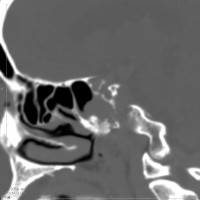

CTでは,斜台から左蝶形骨にかけて不規則な骨破壊像がみられます。

骨をみているCTです。鞍背からsphenooccipital synchondrosisまでの斜台骨皮質が失われています。かなり特徴的な所見です。